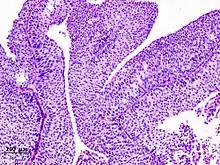

Transitional cell carcinomas are mostly papillary (70%,[2] and 30% non-papillary).[2]

The 1973 WHO grading system for transitional cell carcinomas (papilloma, G1, G2 or G3) is most commonly used despite being superseded by the 2004 WHO[14] grading for papillary types (papillary neoplasm of low malignant potential [PNLMP], low grade, and high grade papillary carcinoma). High-grade carcinoma typically displays more pleomorphism, multiple mitoses, euchromatin and relatively prominent nucleoli, and uneven distribution of nuclei.

Transitional cell carcinoma, being low-grade to the left, and high-grade to the right. H&E stain

Papillary transitional cell carcinoma, low grade